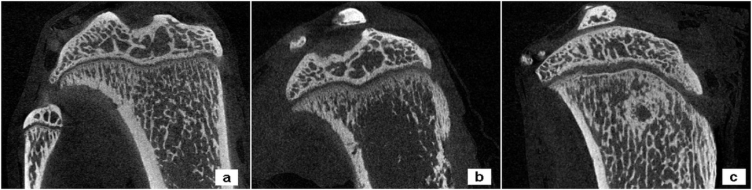

Gli esprimenti nel ratto prima

Fig. 2

Fig. 3

e i trattamenti eseguiti su pazienti affetti da localizzazione ossee Fig. 4 Fig. 5 Fig. 6

hanno permesso già di ottenere dei risultati confortanti per il trattamento delle metastasi ossee.